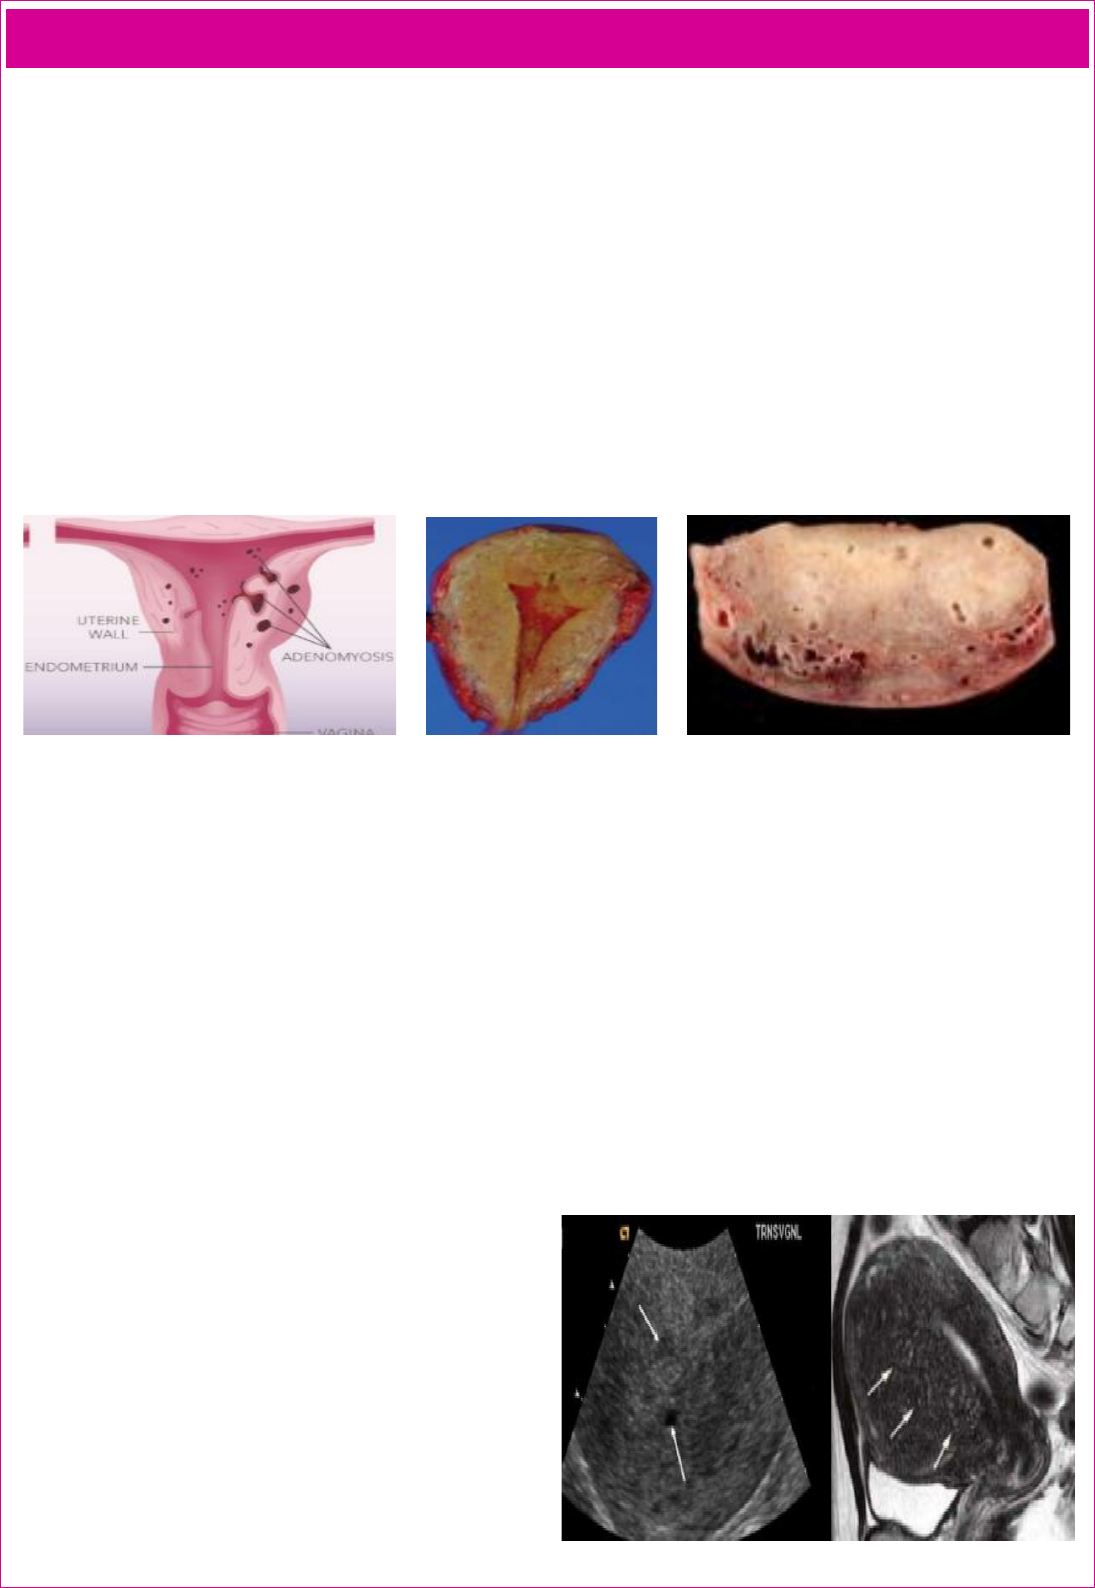

• Macroscopia: aumento difuso de miométrio sem nodulações. Ao corte encontra-se áreas porosas com conteúdo hemático ou seroso.

• Microscopia: ilhas de tecido endometrial no interior do miométrio em profundidade variável (aspecto de dúvida).

DIAGNÓSTICO/EXAMES COMPLEMENTARES

• A identificação da zona juncional, uma linha regular com

espessura menor ou igual a 5mm que determina o limite entre

miométrio e endométrio, possibilita o diagnóstico não-

invasivo da doença. Os avanços recentes das técnicas de

imagem como a ressonância nuclear magnética (RNM) e a

ultrassonografia (USG) permitiram o estudo da adenomiose

em mulheres com manutenção do útero e assim entender a sua

história natural. O diagnóstico clínico é apenas de presunção.

o Ultrassonografia transvaginal (sensibilidade de 92% e

especificidade de 83%) é considerado o padrão ouro de

triagem (realidade atual), sendo o exame de imagem

indicado como primeira linha para o diagnóstico de

adenomiose.

o Ressonância magnética (sensibilidade de 90% e

especificidade de 93%) é considerado o padrão ouro para

diagnóstico, principalmente a contrastada. Delineia a

localização e extensão das lesões e a diferenciação entre

leiomiomas e adenomiomas, sua mais importante

contribuição. O parâmetro de mensuração da zona

juncional mioendometrial na RM é atualmente a melhor

referência para o diagnóstico de adenomiose.